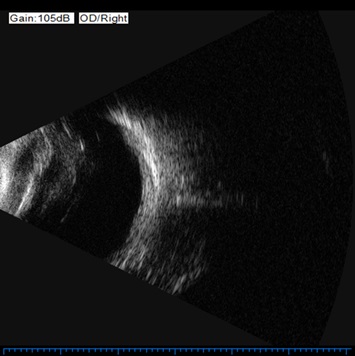

Так выглядит ультразвуковая картина при воспалении в заднем отрезке глаза

Так выглядел глаз под микроскопом